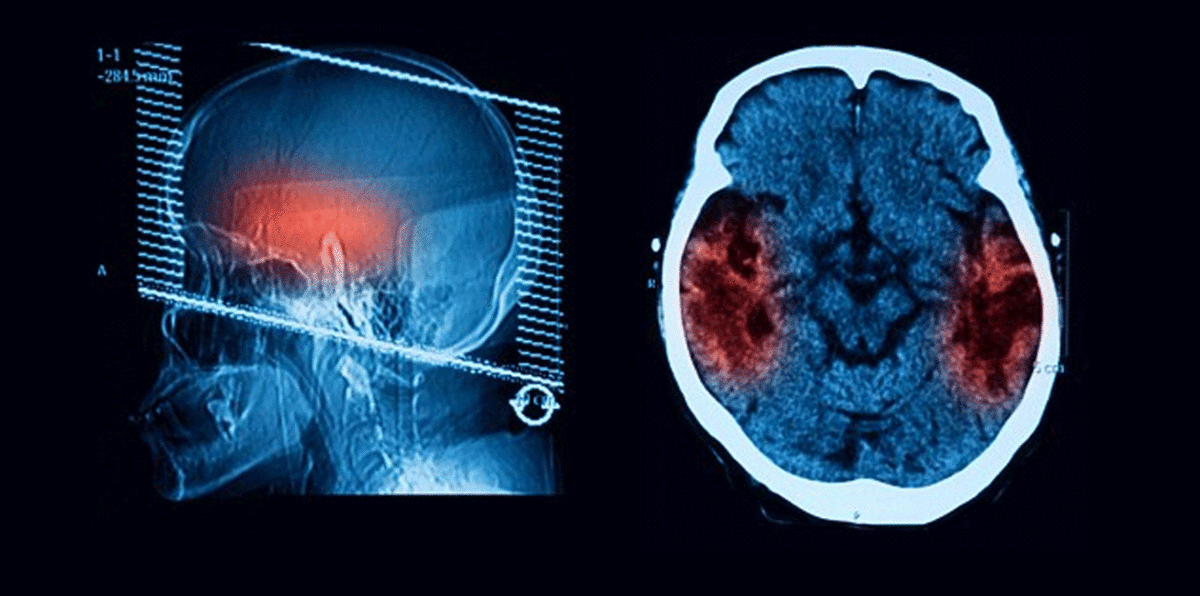

علماء ينجحون في علاج مرض الزهايمر لدى الفئران

نجحت مجموعة من العلماء الأمريكيين في علاج الزهايمر لدى فئران تجارب، عبر استئصال خلايا "الزومبي" في الدماغ.

وتُعرف تلك الخلايا طبيًا بالخلايا المتشيخة، والتي تفقد قدرتها على الانقسام، وتتراكم في جميع أنحاء الجسم مع التقدم في السن، وقد أطلق عليها أيضًا اسم "الزومبي"؛ لأنها لا يمكن أن تموت، ولكنها في الوقت ذاته لا تستطيع أداء وظائف الخلية الطبيعية.

وبحسب العلماء، فإن منع هذا التراكم يحول دون تكون بروتين سام يدعى "تاو"، والذي يؤدي إلى ظهور أعراض مرض الزهايمر، وبالتالي الاحتفاظ بخلايا الدماغ والذاكرة.